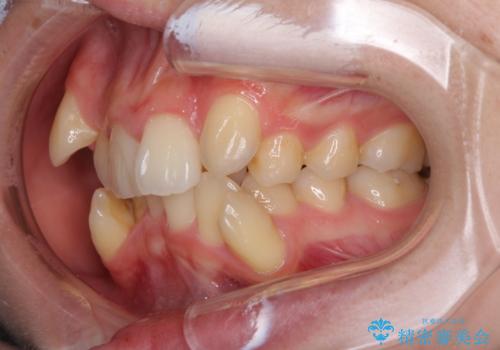

気になる八重歯を治したい ワイヤー装置での抜歯矯正

- 上下の八重歯や乱杭歯を気にして来院され患者様です。

スペースを確保するため、上下左右の第一小臼歯を抜歯し、ワイヤー装置に矯正することとしました。